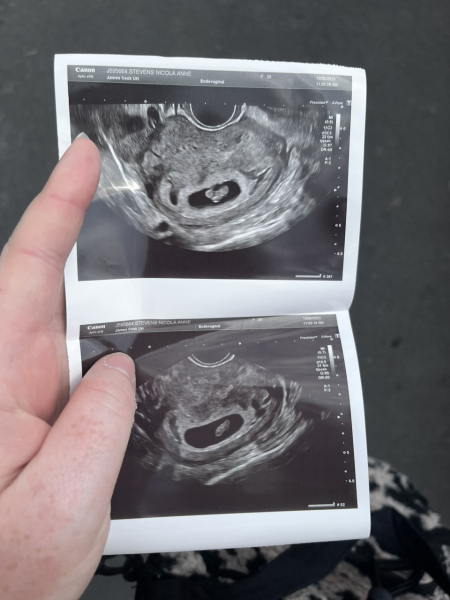

@ChloeN the pictures I have are really good quality...I think 🤷‍♀️😂 I would post but don't know if it's allowed? Although I could just send you them 😂

You can post them @Brokenpancreas94 👌

Aw cute pic @Brokenpancreas94